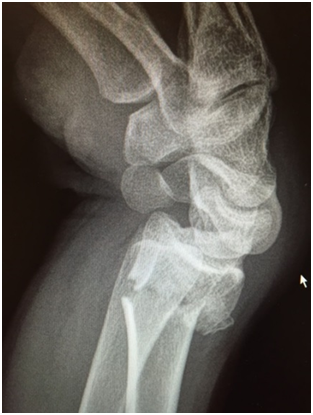

Surgical fixation can take the form of plating the wrist. This will involve an incision on the palmer side of the wrist, putting the fragments of bone back in the right place and then holding them in place with a plate. This allows earlier mobilisation of the wrist (less time in plaster). There are surgical risks which your surgeon will discuss with you and sometimes (but not always) it is necessary to remove the plate at a future date.

The main advantage of treatment in plaster is that there is no surgical risk. However this is not suitable for all as the broken fragments of bone need to be well aligned. A degree of malunion may result. Your consultant will discuss suitable treatment options with you fully.